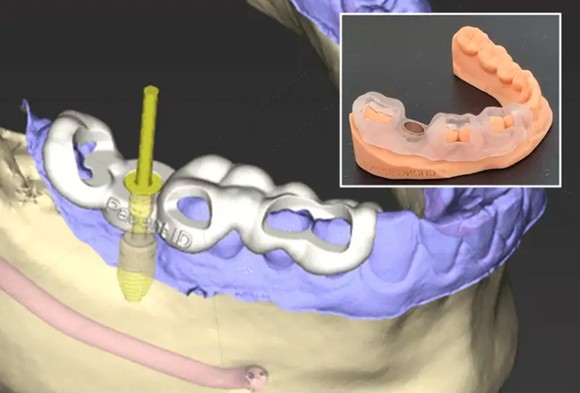

Assessment & Intraoral Scan to see your teeth in 3D

Digital simulation shows exactly where your implant will be and what your final result will look like.

Implant Placement using surgical guides for precision, the titanium implant is placed into your jawbone, typically 30-60 minutes with local anaesthesia.